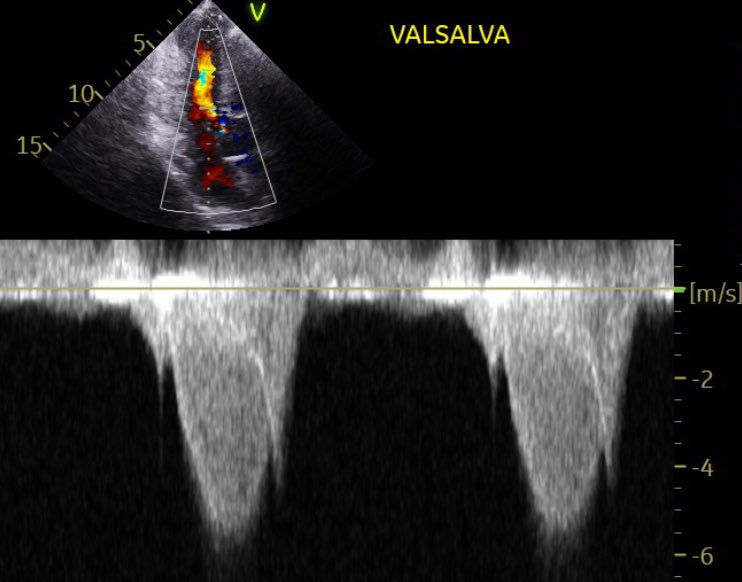

A striking example of double-site obstruction in hypertrophic cardiomyopathy. The apical view demonstrates color Doppler flow acceleration in the LVOT with systolic anterior motion of the mitral valve during Valsalva. The CW Doppler reveals two distinct peaks — the first